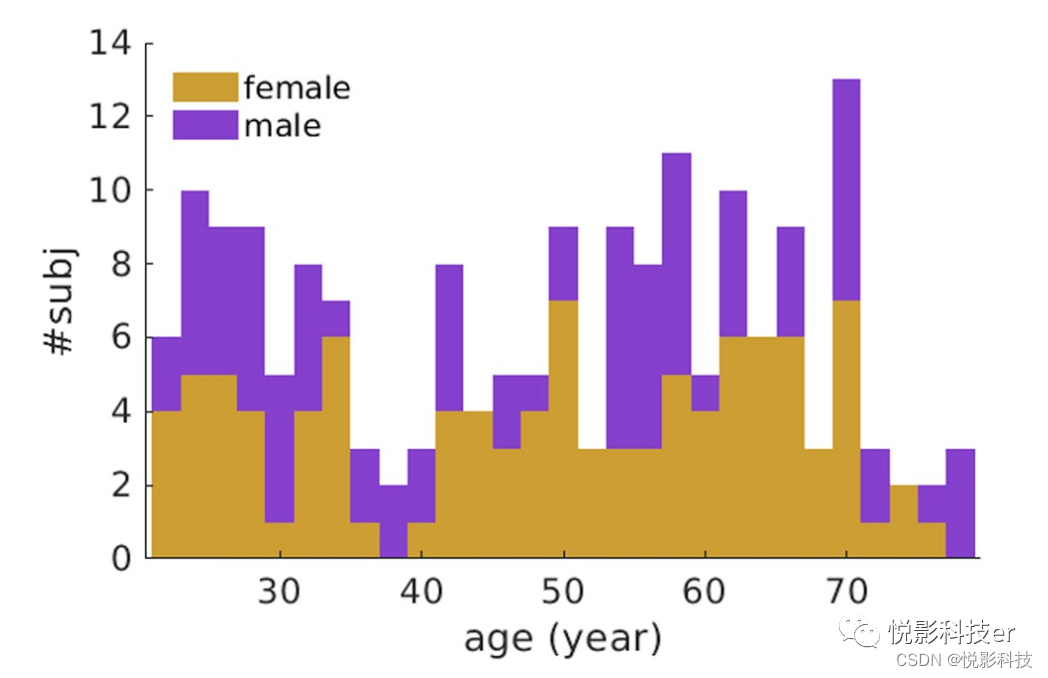

该研究由新加坡国立大学机构审查委员会批准,所有参与者在参与前均提供书面知情同意。本研究招募了214名年龄在22岁至79岁之间的健康中国受试者。当父母和祖父母都是中国人的时候,中国民族就被定义了。排除以下条件的受试者:(1)重大疾病/手术(心、脑、肾、肺手术);(2)神经或精神障碍;(3)学习障碍或注意力缺陷;(4)头部损伤伴意识丧失;(5)身体上/内不可拆卸的金属物体,如心脏起搏器;(6)糖尿病或肥胖;(7)简易精神状态检查(MMSE)得分低于24分。此外,本研究采用三种脑成像模式,包括t1加权MRI、静息态fMRI (rs-fMRI)和小头部运动的高角度分辨率弥散图像(HARDI)。因此,本研究共纳入180名受试者,年龄22 ~ 79岁(男性77人,女性103人)。图1显示了本次研究中受试者的年龄和性别分布。

图1 性别和年龄分布